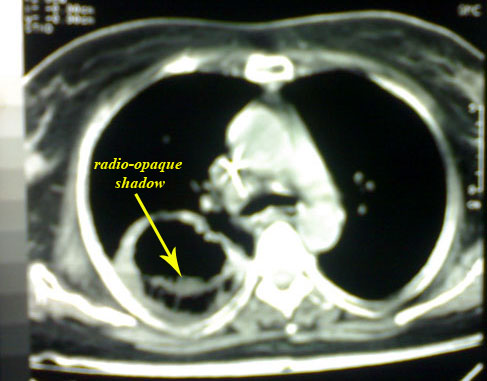

C.T. chest revealed:

-right thick-walled cavity lesion with radio-opaque shadow.